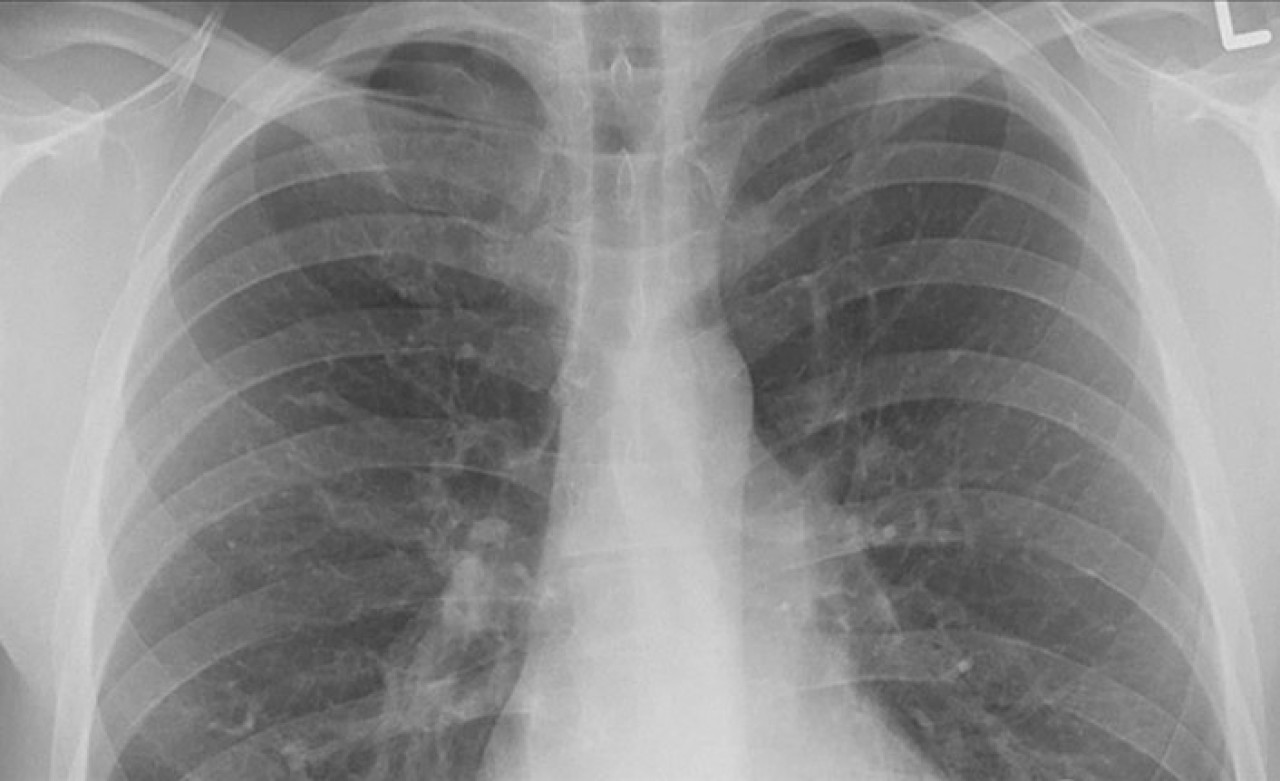

Genellikle akciğer kanserinin neden olduğu bulgu ve şikayetlerin oluşumu birkaç yıl alıyor ve bu nedenle hastalık ileri evreye gelinceye kadar fark edilemeyebiliyor. Kontrol veya başka bir rahatsızlık nedeniyle çekilen akciğer grafisinde kanser teşhis edilebiliyor, erken teşhis tedavide başarı olasılığını artırıyor.